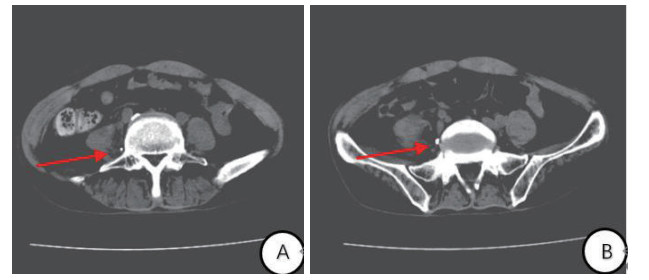

1.2 诊治经过及临床转归入院后给予高压氧治疗每日2 h(2.5 ATA,烟台豪特医用空气加压氧仓)、呼吸机辅助呼吸、营养脑细胞、抗感染等综合治疗。为建立肠外营养通路,采用Seldinger穿刺法行右侧股静脉双腔导管置入术,导管型号为:河南驼人牌3-7Fr-20 cmⅡ型。先后给予静脉泵入去甲肾上腺素、20%脂肪乳、复方氨基酸等药物治疗。入院后7 d出现反复低热,体温多波动在37.5~38℃之间,查血PCT 0.02 ng/mL、CRP 16 mg/L,局部分泌物和血培养未见异常。换药时可见导管皮肤处周围有黄色分泌物,静滴进口左氧氟沙星注射液0.5 g/d后无明显好转。入院后12 d复查CT提示:腹膜后积液,积液主要位于腰大肌和腰椎间隙,股静脉导管异位(图 1)。遂拔出中心静脉导管,B超定位下经皮穿刺引流腹膜后积液(图 2),可见淡黄色液体,共引流600 mL,患者2 d后体温逐渐恢复正常。

| 图 2 腹部CT横断面(A, B)股静脉导管尖位置 |

股静脉置管常见并发症包括局部感染、空气栓塞、局部出血或水肿、静脉穿孔、经或淋巴管受损[9-11],但是血管外异位国内外文献罕见报道。本病例中股静脉导管血管外异位且未被早期发现,归咎于下列因素:(1)操作医生动作粗暴,进入导丝步骤用力过猛穿破血管,且进入股静脉血管内导丝过长,从而引导导管至血管外。(2)由于置管后无大出血,推测导管可能先进入腰深静脉后穿出血管。(3)医生置管后和护士每日输液前回抽静脉血通畅,误导医生认为导管位于血管内。实际可能为导管侧孔位于血管内,而导管尖位于血管外。(4)医生穿刺成功后未及时行B超定位导管位置[12]。